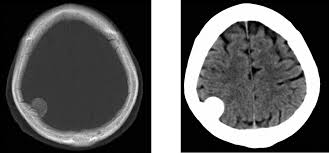

Acetato de medroxiprogesterona de depósito y riesgo de meningioma

08 septiembre 2025

En este estudio, las mujeres que recibieron acetato de medroxiprogesterona de depósito presentaron un mayor riesgo relativo de diagnóstico posterior de meningioma, especialmente con exposiciones prolongadas e inicio de la medicación a edades más avanzadas. El elevado número necesario para producir daño sugiere un bajo riesgo clínico general. JAMA Neurology, 2 de septiembre de 2025.